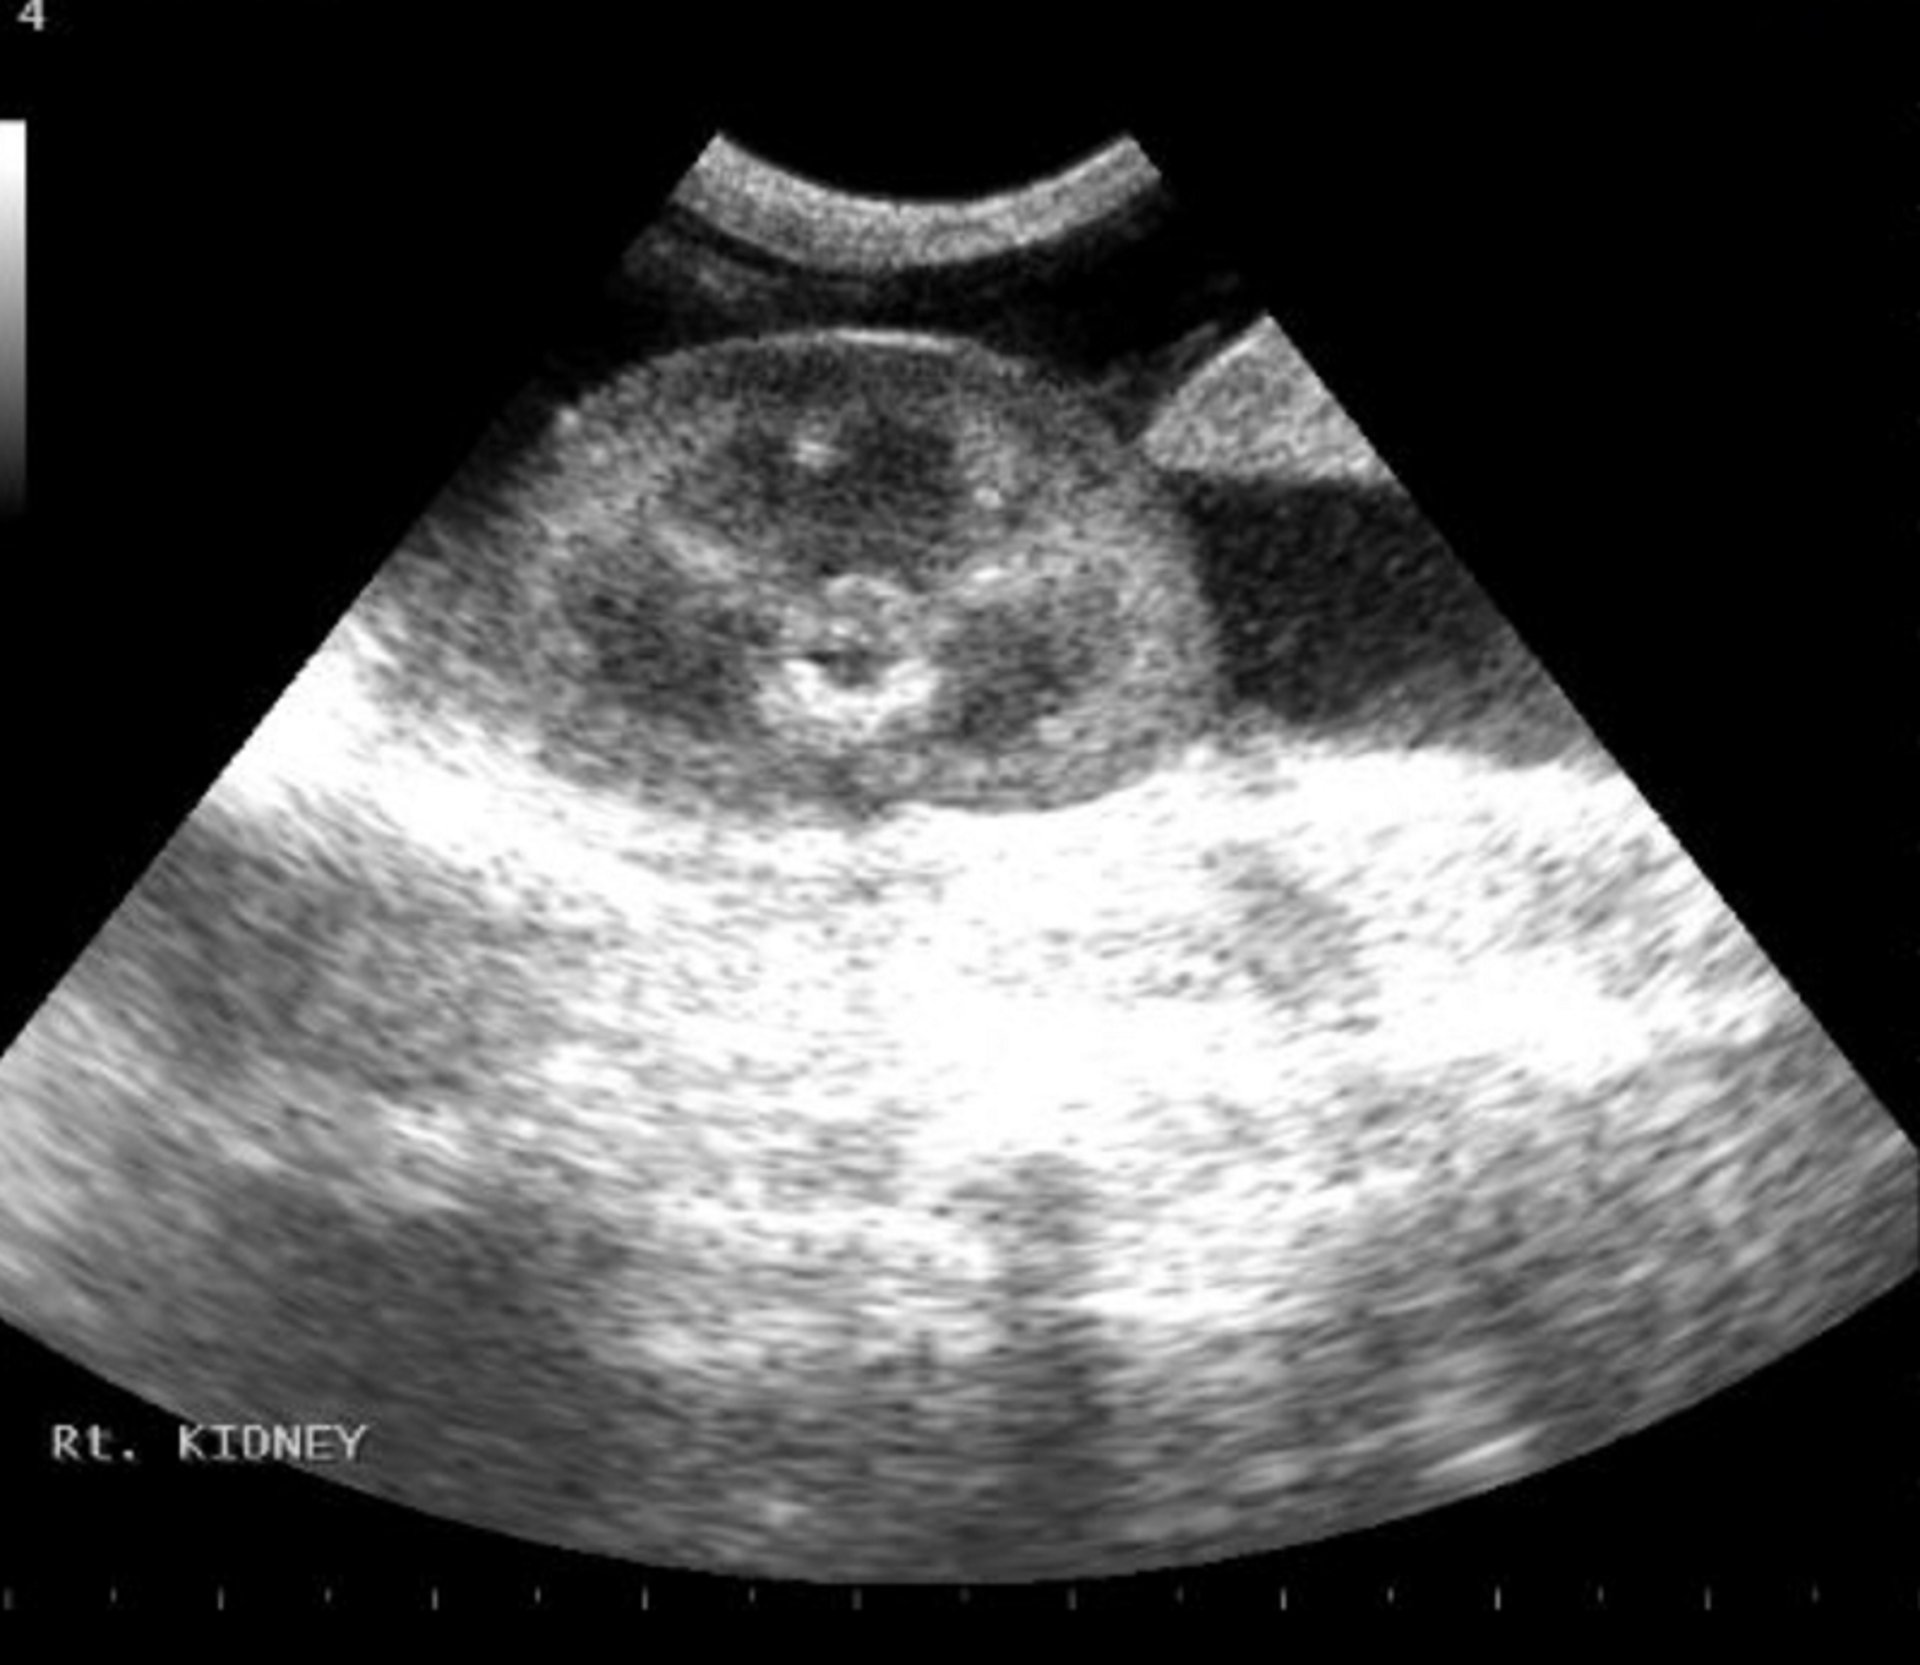

Image from an abdominal point-of-care ultrasound scan demonstrating an accumulation of fluid (black/anechoic) around the right kidney.

Courtesy of Dr. Andrew Linklater.